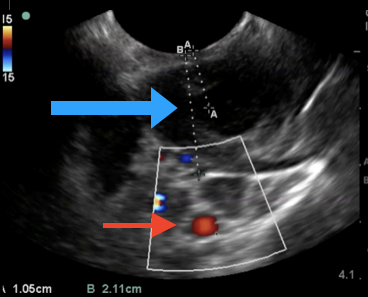

While imaging is not necessary to diagnose peritonsillar abscess, the diagnosis in patients with undifferentiated sore throat with concern for other deep-seated neck space infections may be facilitated with advanced imaging, such as ultrasound or computed tomography (CT) with intravenous (IV) contrast.3 A bedside ultrasound may be performed via the traditional intraoral technique and/or submandibular technique with a sensitivity of greater than 90%. (See Figure 2.) The classic finding with peritonsillar abscess on ultrasound is a discrete fluid collection with heterogeneous constituent with an irregular border.4 Ultrasound also may help with procedural guidance and landmark evaluation of the distance to the center of the abscess as well as the location of the surrounding vasculature.

Figure 2. Point-of-Care Ultrasound with an Endocavitary Probe to Evaluate the Posterior Oropharynx |

A peritonsillar abscess (blue arrow), carotid artery (red arrow), and relative distances to each. Courtesy of Daniel Migliaccio, MD. |